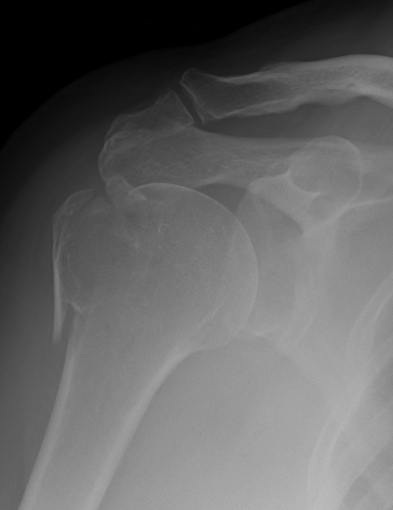

proximal humerus fracture Background ORIF with locking plate Arthroplasty Greater tuberosity fractures Lesser tuberosity fractures / avulsions Book traversal links for Proximal humerus fractures ‹ Pectoralis Major Tears Up Background ›